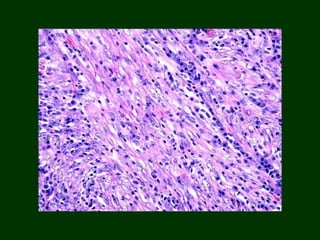

HISTOPATHOLOGY

Non- encapsulated, poorly circumscribed, infiltrative lesion with a fascicular

growth pattern, usually striated musculature

Cellular proliferation of spindle shaped cells that are arranged in streaming

fascicles & associated with variable amount of collagen.

No atypia, mitotic figures.

Slit like vascular spaces seen